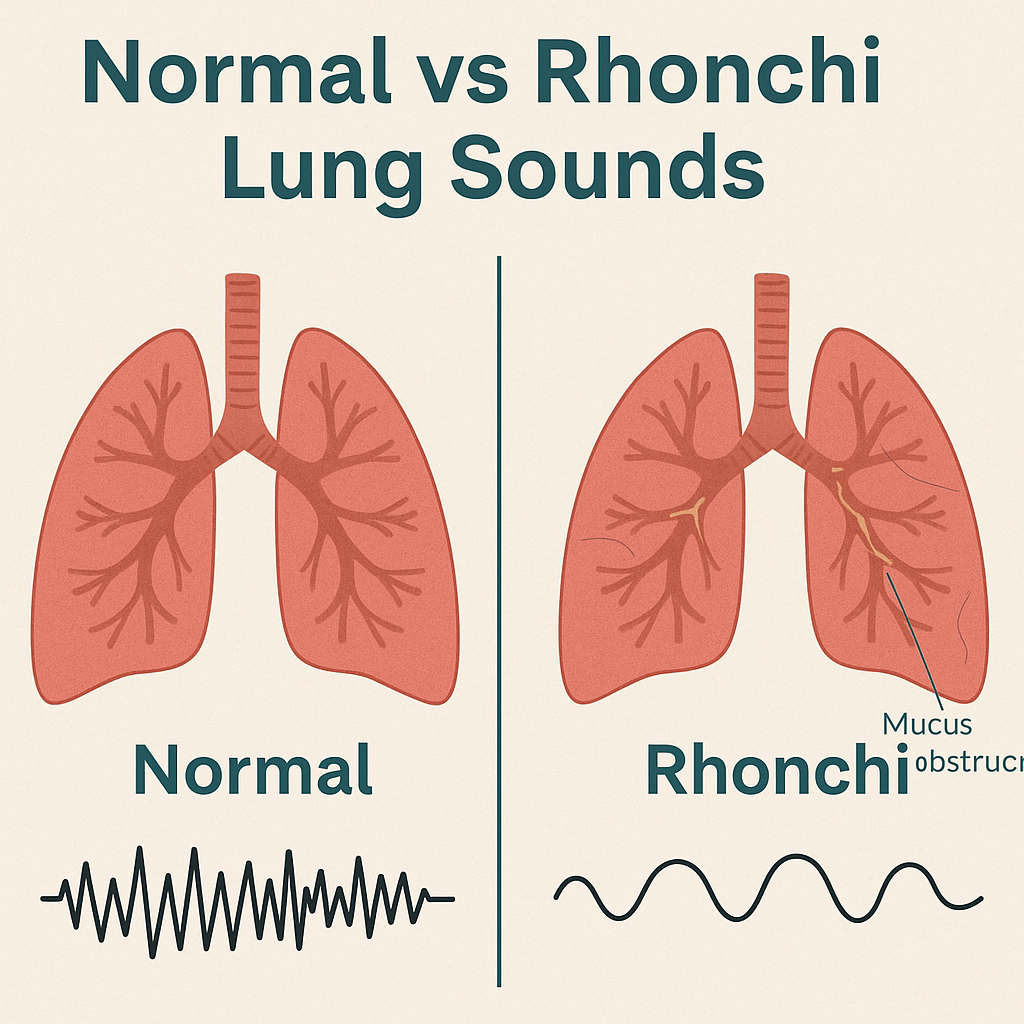

Rhonchi (રહોન્કાય) :

- રહોન્કાય (Rhonchi) એ એક અબનોર્મલ કન્ટિન્યુઅસ બ્રેથ સાઉન્ડ (Abnormal Continuous Breath Sound) છે, જે સામાન્ય રીતે લો-પિચ્ડ (Low-pitched) અને સ્નોરીન્ગ/ ગર્ગલીન્ગ (Snoring / Gurgling) જેવા અવાજ તરીકે સંભળાય છે.

- આ અવાજ મોટાભાગે એરવે (Airway) માં મ્યુકસ (Mucus) અથવા અન્ય સિક્રેશન (Secretions) ભરાય જવાથી બને છે, ખાસ કરીને મોટા બ્રોન્કી (Large Bronchi) માં. જે સામાન્ય રીતે Expiration (શ્વાસ છોડતી વખતે) સંભળાય છે, ક્યારેક Inspiration દરમ્યાન પણ.